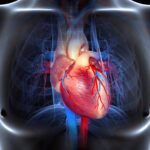

La intoxicación por bloqueadores beta-adrenérgicos es un fenómeno clínico complejo que se asocia a la administración excesiva o inadecuada de fármacos que actúan sobre los receptores beta-adrenérgicos del sistema nervioso…